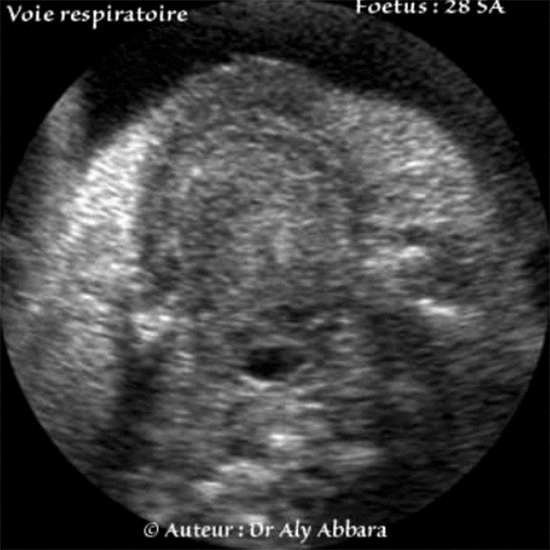

Pharynx - Foetus de 28 SA

Voie respiratoire haute : pharynx - épiglotte - larynx

Coupes axiales au niveau de la cavité buccale et le cou, centrées sur le pharynx et le larynx

(Fœtus âgé de 28 SA).

• Coupes échographiques axiales centrées sur la partie supérieure de la voie respiratoire ; elles permettent la mise en évidence successivement, de haut vers le bas :

• En avant, la langue occupant la cavité buccale et en arrière, le pharynx buccal libre ;

• Ensuite, l'épiglotte tout en arrière de la base de langue, elle fait saillie dans le pharynx en avant ;

• Puis, l'épiglotte surmontant le larynx ;

• Enfin l'ouverture du larynx (ou la glotte) limitée bilatéralement par les deux cordes vocales droite et gauche.